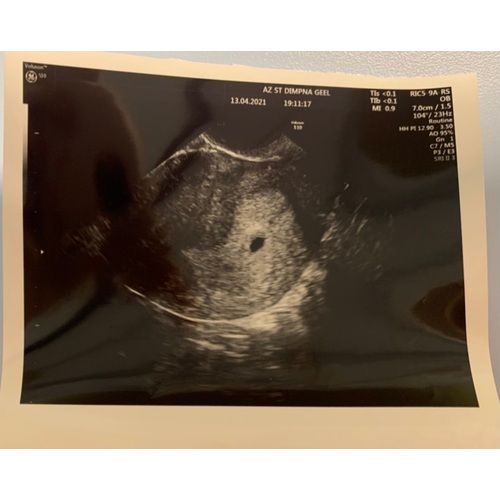

Met 5+1 had ik ook alleen een zwarte vlek. 2 weken later zag ik een klein kindje met hartslag

Ik had dezelfde echo bij 4+5, en de echo erop zag je een vruchtje bij 8 weken met hartslag enzo.